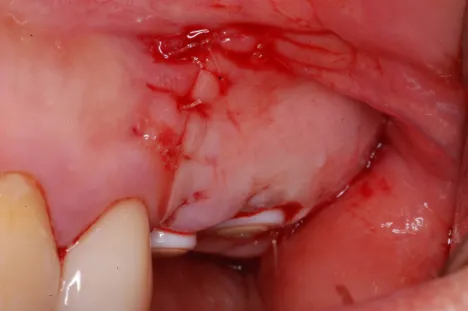

Dr.Megas_Fig.5

Fig. 5. Post-suturing